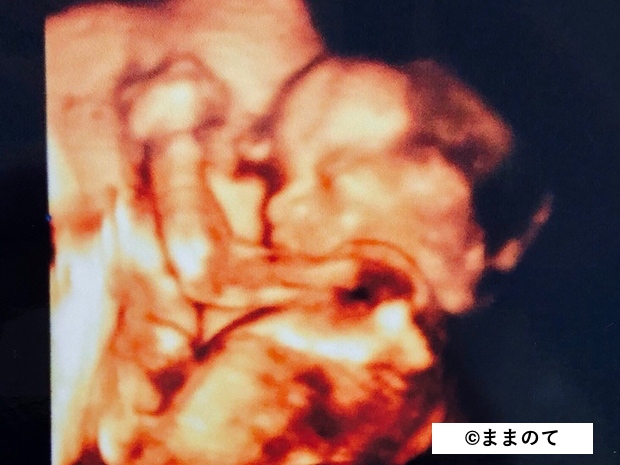

3Dエコー

3Dエコーは平面でとらえる2Dエコーに「高さ」の座標を加え、3次元で画像化しています。このため、映し出された映像は立体的に見えます。妊娠時の3Dエコー撮影は記念撮影的な意味合いが強く、妊婦健診を受けている病院で3Dエコーの設備がない場合、他の病院の外来を受ける妊婦さんもいます。タイミングが合えば赤ちゃんの表情をクリアな画像で見られますよ。

一方で3Dエコーは年々技術革新が進み、身体の内部にある器官をよりリアルな状態でとらえられるようになりました。そこで、現在では一般的な妊婦健診で3Dエコーが用いられるケースが出てきています。

4Dエコーは3Dエコーに「時間」の座標軸が加わります。3Dエコーは静止画をスライドショー的につないで画像化していますが、4Dエコーでは動画で赤ちゃんの様子を見ることができます。

赤ちゃんの向きや姿勢によっては、赤ちゃんがあくびや指しゃぶりをする様子が映るかもしれません。

産婦人科で導入している機械の中には、3Dエコーと4Dエコーがスイッチで切り替えられるものがあります。3Dエコーで観察して条件が良いと判断されれば、4Dエコーによる撮影に切り替えてくれる病院もあるようです。

赤ちゃんの器官が成熟し始め、耳が聞こえるようになってきます。そのため、人間らしい仕草をしたり、音に驚いたりするようになります。

身長は約35cm、体重は約1,000gになります。赤ちゃんの大きさが3Dエコーの撮影に最も適している時期で、タイミングが良ければ指しゃぶりやあくびをしている様子が見られるかもしれません。